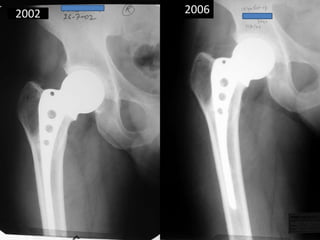

• 22 years old male had RTA – fracture neck

femur. 1986

• Operated by multiple Knowles Pins.

• Broken pins noted – 1988 – fracture united.

• AVN – 1990 – AMP done.

• Pain in anterior thigh 2002 due to broken

stem.

• Last follow up 2006.

2002 2006